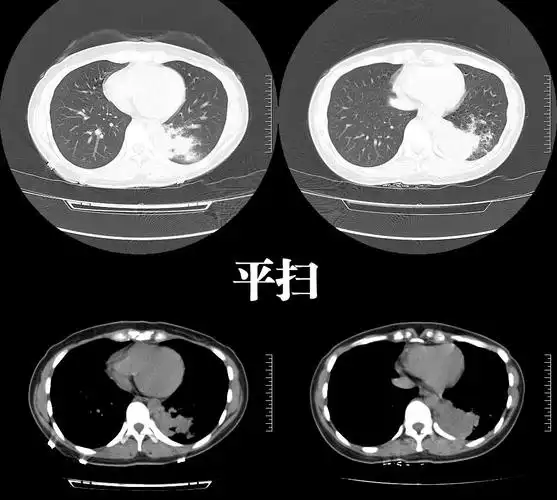

肺隔离症影像表现

【影像读片】肺隔离症?